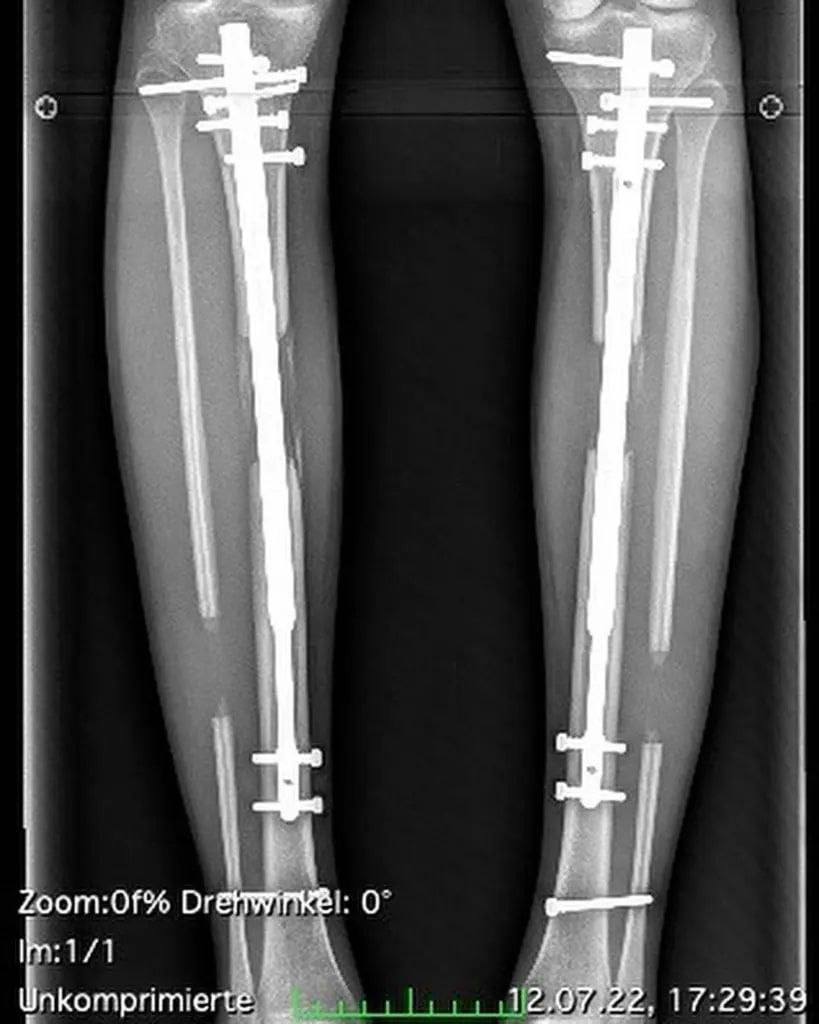

Для ее осуществления она перенесла две операции по вставке железных штифтов в берцовые кости, которые предварительно ломались хирургическим путем. Тереза рассказывает, что «ноги стали очень гибкими, и у меня появилось больше места для маневра в постели».